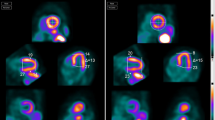

The purpose of our study was not to correlate our results with that of catheterization data or clinical outcome but simply to determine if a misalignment artifact, caused primarily by cardiac emission data mapped onto lung transmission data, was present in our institutional protocol with adenosine. In our series, 29% of rest and 24.6% of adenosine stress studies demonstrated some degree of misalignment, a similar frequency to that of Loghin and coworkers in which dipyridamole stress was employed [7]. Of the 17 studies in which there was stress misalignment, pre- to post-realignment comparison revealed that in four there was a significant change in clinical interpretation with manual realignment. Figures 2 and 3 are examples from a clinical case subsequent to collection of the above data in which an artifactual defect was recognized and corrected, which changed the reading from “ischemia” to “no significant abnormality.”

QC program (a), multiplanar slices (b) and polar images (c) from a patient with misalignment of cardiac activity (straight arrow in a). The QC display shows the binarized emission data (red) overlaying the transmission data (gray). The algorithm has determined that 125 pixels occupying 11.2 ml from the emission image lie within the left lung of the transmission image. The user can shift or rotate the transmission image in any of the planes to correct this problem (see Fig. 3). Note large apparent reversibility in lateral wall (angled arrows in b). This degree of artifact is unusual in our experience.

Same patient as in Fig. 2 after correction of misalignment. Note corresponding QC program (a), multiplanar slices (b) and polar images (c) in which the artifactual lateral wall reversibility has normalized (angled arrows in b). A small partially reversible inferior wall defect is not clinically significant in this patient with cardiomyopathy.